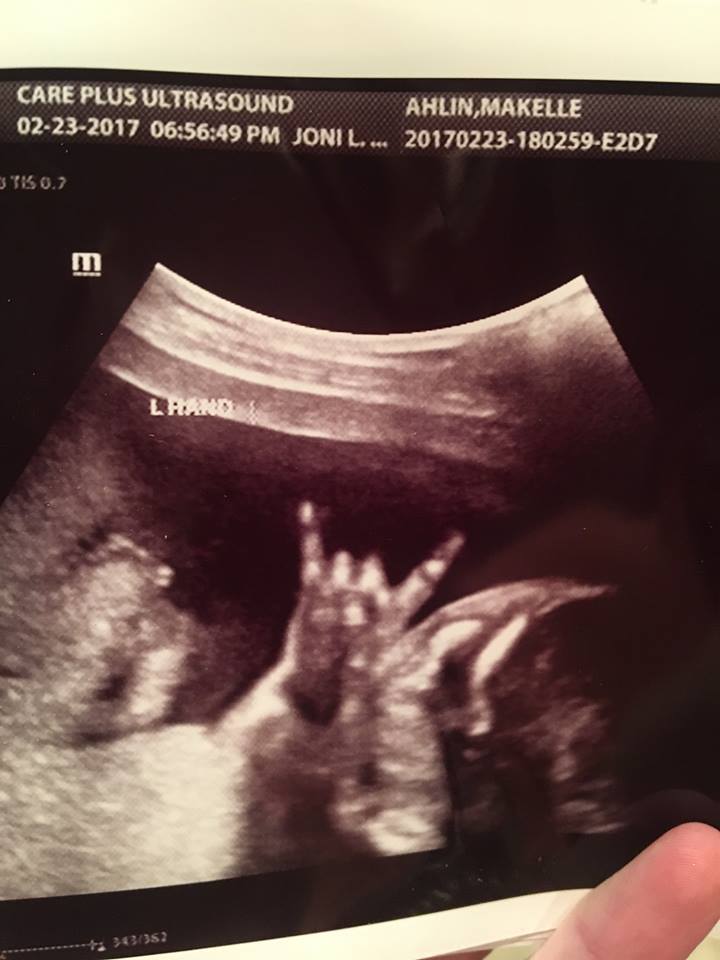

Một anh chồng ở Mỹ đưa vợ đi siêu âm kiểm tra sức khỏe thai nhi ở tuần thứ 22. Em bé trong bụng mẹ giơ tay như ngôi sao nhạc rock. Theo nhân viên siêu âm thì chắc bé muốn gửi thông điệp gì cho ba mẹ chăng.

Một cặp vợ chồng Mỹ đã bị sốc khi nhìn thấy con của mình giơ tay kiểu “rock n roll” trong khi siêu âm.

Theo Mirror, cặp đôi Jared và Makelle Ahlin ở bang Utah nước Mỹ đi siêu âm lúc Makelle mang thai 22 tuần tuổi. Họ đã chia sẻ những hình ảnh đặc biệt này với bạn bè trên Facebook.

Hình ảnh siêu âm con của cặp đôi Jared và Makelle Ahlin

Mẹ Makelle nói với CBS News: "Chồng tôi là người đầu tiên phát hiện ra điều này. Anh ấy nói với nhân viên siêu âm “Chiếu lại” khi cô ấy tiếp tục làm việc.

Sau đó, Jared yêu cầu nhân viên chụp lại bức ảnh đặc biệt. "Anh ấy đã rất phấn khởi với những gì mình nhìn thấy”, Makelle nói.

Cặp vợ chồng đã xem đi xem lại video nhiều lần. Nhân viên siêu âm nói đùa với họ: "Em bé chắc hẳn đang muốn gửi thông điệp gì đó cho các bạn".